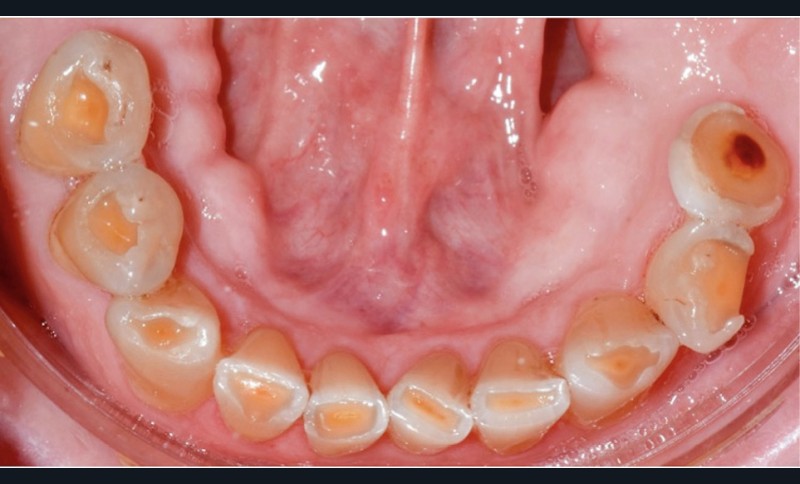

Le cas clinique présenté ici illustre cette démarche thérapeutique. À la suite d’un diagnostic de cancer des voies aérodigestives supérieures, un patient de 68 ans a bénéficié d’un traitement par radiothérapie cervico-faciale, terminée depuis plus de 2 ans. Il souhaite désormais retrouver une réhabilitation fonctionnelle et esthétique de sa cavité orale. Il indique que le délabrement de ses dents antérieures est à l’origine d’un important préjudice esthétique, qui l’a conduit à ne plus sourire. De plus, ses dents absentes réduisent fortement ses capacités masticatoires. Ces différents facteurs influent donc directement son estime de soi et sa qualité de vie, paramètres clés de la rémission dans le cadre oncologique. À l’examen clinique, il présente une perte de calage postérieur, avec des édentements terminaux secteur 2 et 4, ainsi que de volumineuses pertes de substance au niveau des dents présentes (fig. 1).